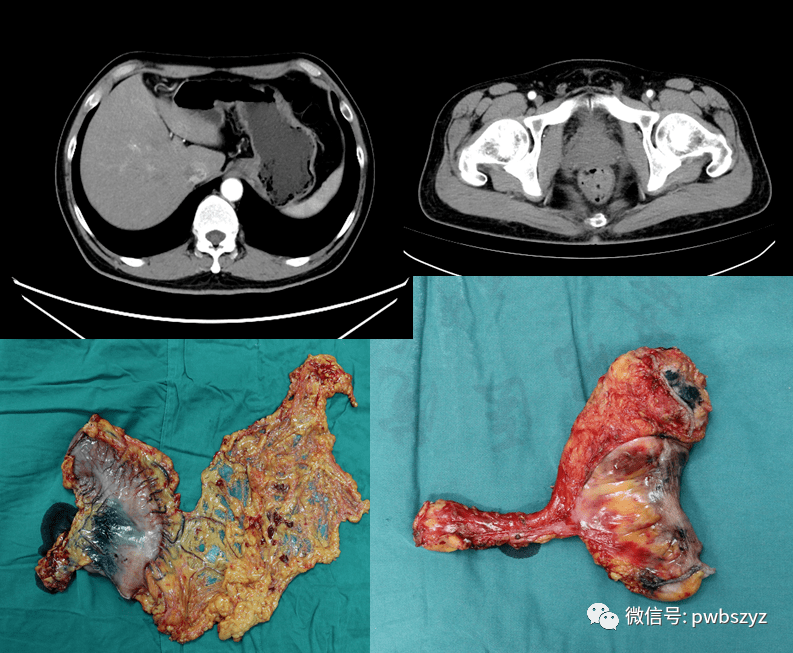

病例(26)--左侧腹膜后巨大肿瘤切除 - 好大夫在线

图片尺寸1600x1200